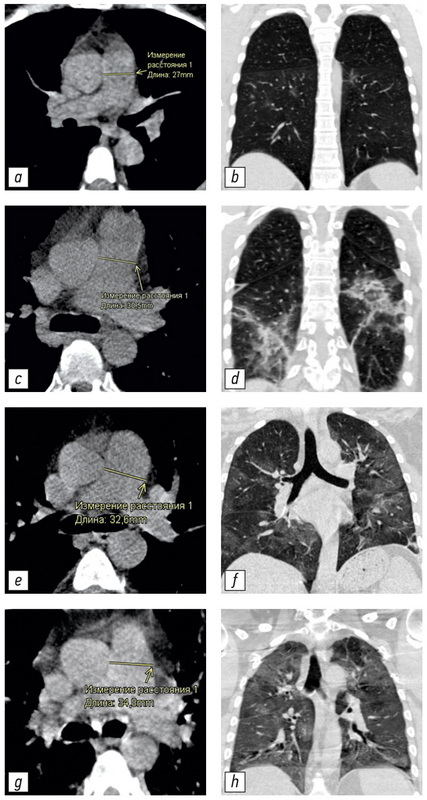

BACKGROUND: Computed tomography is the method of choice for assessing the volume of lung damage in viral pneumonia, including those associated with COVID-19. In addition, computed tomography can determine the main vessels size of the thorax. This allowed us to analyze the relationship between the severity of COVID-19 and the changes in the diameters of the pulmonary artery (PA) and ascending aorta (Ao). Dilation of the PA is a sign of pulmonary hypertension. The study of these patterns may be of clinical significance in determining the treatment tactics and prognosis of the course of COVID-19 disease.

MATERIALS AND METHODS: This study is a single-centered, cross-section, continuous, uncontrolled study performed on a group of patients (n=511, 267 men, median 59 years, IQR 49.0–65.0, ages 31–84 years) who were treated in a temporary hospital to treat patient with COVID-19. During hospitalization all patients were examined by CT scan of the chest. All studies were carried out using a mobile CT scan system Airo TruCT (Stryker, USA). The degree of damage to the lung tissue was assessed using the CT volume scale 1–4. Measurement of the LA and Ao diameters was carried out using standard instruments of the radiologist’s CT workstation perpendicular to the long axis of the vessel.

RESULTS: The following statistically significant regularities were obtained: the detection of a dilated pulmonary artery (PA) and an increased PA/Ao ratio correlated to an increase in the degree of lung damage in COVID-19 (Kruskal-Wallis test, K-W p <0.001; median test, MT p <0.001), the diameter of the ascending aorta (Ao) significantly increases with the patient’s age (K-W p <0.001; MT p <0.001). An insignificant correlation between an increase in the diameter of the pulmonary artery (PA) and the patient’s age (K-W p=0.094; MT p=0.311) and an insignificant correlation between detection of a change in aortic (Ao) diameter and the degree of lung damage (K-W p=0.061; MT p=0.165) were shown. In groups with a severe course of the disease and a large volume of lung lesions (CT-3 and CT-4), a significantly greater number of patients with signs of pulmonary hypertension (detection of the dilated pulmonary artery: 29 mm and more) was shown for all age groups.

CONCLUSION: The study showed that PA dilatation and increased PA/Ao diameter ratio were significantly associated with increased pulmonary lesion volume in COVID-19 in all age groups.